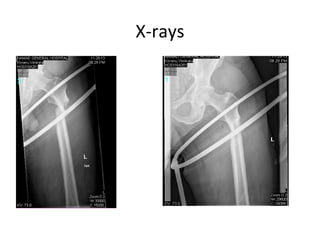

Treatment

• Operative

– intramedullary nailing (usually cephalomedullary)

• indications

– historically Russel-Taylor type I fractures

– newer design of intramedullary nails has expanded indications

– most subtrochanteric fractures treated with IM nail

– fixed angle plate

– surgeon preference

– associated femoral neck fracture

– narrow medullary canal

– pre-existing femoral shaft deformity